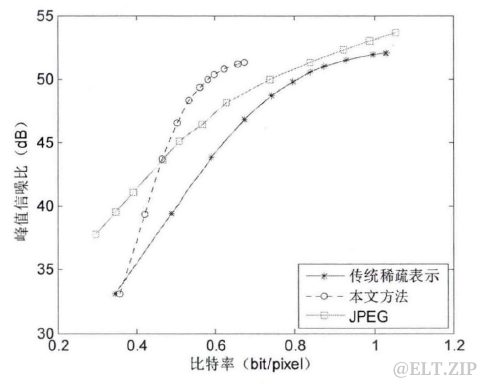

算法测试

- 将上述提出的基于稀疏表示的序列图像压缩方法与传统的基于稀疏表示的图像压缩方法、JPEG 压缩方法作对比,图六展示了这几种不同方法的压缩效果。可以看出,本文方法的压缩效果优于传统的基于稀疏表示的图像压缩方法,在

低比特率时 JPEG 压缩效果优于本文方法,在高比特率时该方法压缩效果优于JPEG。考虑到医学图像对图像质量要求很高,也就要求其峰值信噪比较高,基于稀疏表示序列图像的方法在高峰值信噪比的情况下,能够达到优于JPEG的压缩效果。

图六.不同压缩方法的压缩效果比较

总结

- 本文介绍了基于稀疏表示的医学序列图像压缩方法,该方法利用医学序列图像之间的相似性,建立了二次字典和参考索引,实验结果表明,++这种对序列图像进行整体压缩的方法在高峰值信噪比时其压缩效果优于 JPEG 压缩标准++。